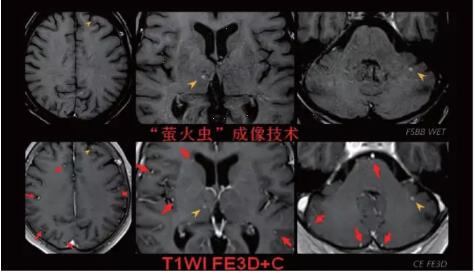

見所未見 微小腫瘤無處遁藏——

“螢火蟲”成像技術 顱內(nèi)腫瘤微小病灶檢出新發(fā)現(xiàn)

此技術主要用于神經(jīng)系統(tǒng)惡性腫瘤,以及其他腫瘤腦轉移瘤篩查。傳統(tǒng)情況下做腫瘤腦轉移篩查,很容易漏掉5mm以下小病灶,臨床發(fā)現(xiàn)后干預治療比較晚,要實現(xiàn)2mm高空間分辨率和超薄層全腦掃描在保證信噪比的情況下需要很長時間大概十多分鐘,而且薄層增強序列顱內(nèi)血管呈高亮信號,會干擾顱內(nèi)小病灶的觀察,血管和小病灶區(qū)分困難。佳能”螢火蟲”成像技術既可以實現(xiàn)高空間分辨率和超薄層(最薄可實現(xiàn)0.2mm)全腦掃描,掃描時間短,2-3分鐘即可實現(xiàn)全腦3D掃描,同時避免了血管高亮信號的干擾,對顱內(nèi)原發(fā)或繼發(fā)的微小腫瘤檢查有重大意義。“螢火蟲”成像技術具有磁敏感效應,對于亞急性血敏感敏感,可以區(qū)分出血和強化的腫瘤。